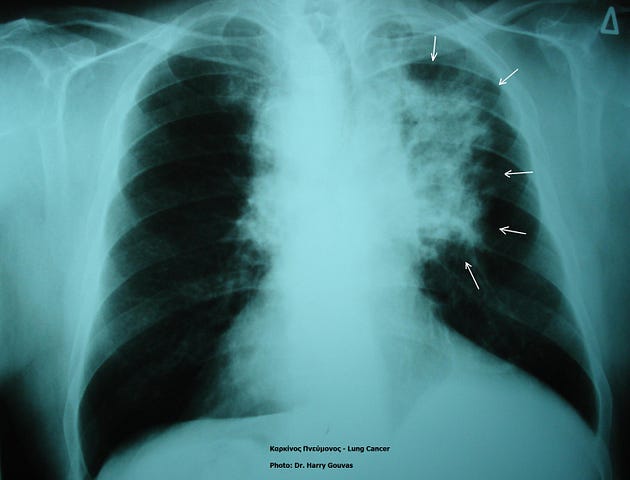

E-patient Dave fue diagnosticado de cáncer al pulmón con metástasis en varias partes del cuerpo. El diagnóstico era concluyente para su médico. No había nada más qué hacer. Dave debía esperar lo peor.

Sin embargo, se hizo cargo y buscó soluciones alternativas.

Fue su propio médico quien le recomendó conectarse a una comunidad online con gente con su mismo diagnóstico. En este espacio, se enteró de un nuevo tratamiento que muchos hospitales no prescribían, pero que terminó por salvar su vida.

Dave dice que se salvó gracias a la red de pacientes y a la información que solo ellos pudieron darle.

“Un tratamiento aprobado y validado que no me lo compartió un establecimiento de salud, sino un grupo de gente con el poder del conocimiento compartido”, recuerda Dave.